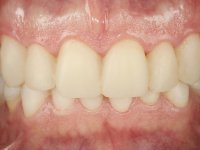

Após análise clínica e imagiológica foi proposto ao paciente recuperar a dimensão vertical da oclusão essencialmente à custa de incrementos oclusais inferiores utilizando “overlays” no sector posterior e facetas no sector anterior. A coroa aparafusada sobre o implante 3.5 seria substituída, no sentido de acompanhar este incremento. Na maxila o dente 2.6 teria extração indicada e posteriormente seria reabilitado com um implante e respetiva coroa. No sentido de reabilitar esteticamente o paciente duma forma minimamente invasiva, foi proposta a colocação de facetas feldespáticas no sector antero-superior. O objetivo de aumentar ligeiramente a D.V.O., teria como função “proteger” eficazmente o sector antero-superior.

Realizado o diagnóstico e tomada a decisão quanto ao tratamento a executar, tornou-se importante definir qual a sequência de trabalho a adotar no sentido de conseguir a reabilitação da D.V.O. (V.D.O), de forma progressiva e equilibrada. Na primeira fase fez-se uma pré-impressão da arcada inferior com silicone tipo “putty” e em seguida realizou-se o preparo dentário de todo o sector posterior. O preparo para os overlays foi feito coronalmente à linha amelo cementaria no sentido de ser o mais conservador possível. A impressão foi feita com técnica de dupla mistura após afastamento gengival realizado com pasta de caulino. A provisória foi realizada com resina composta de polimerização dual. Em laboratório foram realizados os overlays após se ter aberto ligeiramente (1,5mm) a D.V.O. nos modelos montados em articulador semi-ajustável. Simultaneamente o sector antero-inferior foi encerado no sentido de acompanhar este aumento da D.V.O. Também foi confecionada uma chave de silicone translucido para posterior confeção dos provisórios antero-inferiores. Em boca foi primeiro realizada a provisionalização dos dentes anteriores utilizando resina composta previamente aquecida após preparação das superfícies dentárias para a adesão. Foi colocado o dique de borracha para promover o isolamento absoluto e posteriormente foram colados os overlays. Em laboratório foi realizada nova chave de silicone para confecionar os provisórios antero-superiores. Seguidamente em boca foram preparados os seis dentes antero-superiores após colocação do fio de afastamento gengival. Feita a preparação adequada das superfícies dentárias foi realizada a impressão com técnica de dupla mistura e a respetiva provisória. Em laboratório foram confecionadas 6 facetas feldespáticas num modelo de trabalho tipo “Geller”. A provisória foi removida e as facetas foram coladas em boca utilizando um isolamento relativo competente. Esta opção foi tomada em virtude de uma prévia experiencia negativa com a colocação do dique de borracha na mandibula. Após a colagem dos laminados antero-superiores foram dadas 12 semanas para avaliar a adaptação do paciente à nova situação e então iniciar a confeção das facetas antero-inferiores. Após colocação do fio de afastamento gengival. foram feitos os preparos dentários adequados e em seguida foi feita a impressão. Também foi feita a preparação do dente 3.4 que, entretanto, tinha sofrido uma fratura do overlay. As facetas e a restauração do 3.4 foram realizadas num modelo de trabalho tipo “Geller”. Após remoção da provisória, as facetas foram coladas em boca, utilizando um isolamento relativo pelas razões apontadas anteriormente. Após colocação do trabalho o paciente foi reabilitado por outros colegas com um implante na zona do 2.6 e substituição da coroa aparafusada sobre o implante colocado no local do 3.5. Posteriormente surgiram fraturas nos overlays dos dentes 4.7 e 3.7 que foram reabilitados com overlays em Zr.